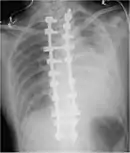

Two chest X-rays: left showing a massive left-sided hemothorax; right showing a massive right hemothorax

A chest X-ray is the most common technique used to diagnosis a hemothorax.[23] X-rays should ideally be taken in an upright position (an erect chest X-ray), but may be performed with the person lying on their back (supine) if an erect chest X-ray is not feasible. On an erect chest X-ray, a hemothorax is suggested by blunting of the costophrenic angle or partial or complete opacification of the affected half of the thorax. On a supine film the blood tends to layer in the pleural space, but can be appreciated as a haziness of one half of the thorax relative to the other.[5] A small hemothorax may be missed on a chest X-ray as several hundred milliliters of blood can be hidden by the diaphragm and abdominal viscera on an erect film. Supine X-rays are even less sensitive and as much as one liter of blood can be missed on a supine film.[24]